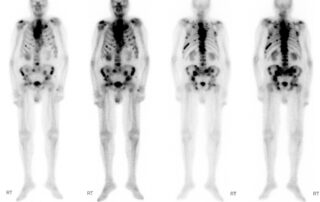

Σπινθηρογράφημα Οστών

Τι είναι το σπινθηρογράφημα οστών Το σπινθηρογράφημα οστών αποτελεί βασική απεικονιστική μελέτη που βοηθά σημαντικά [...]